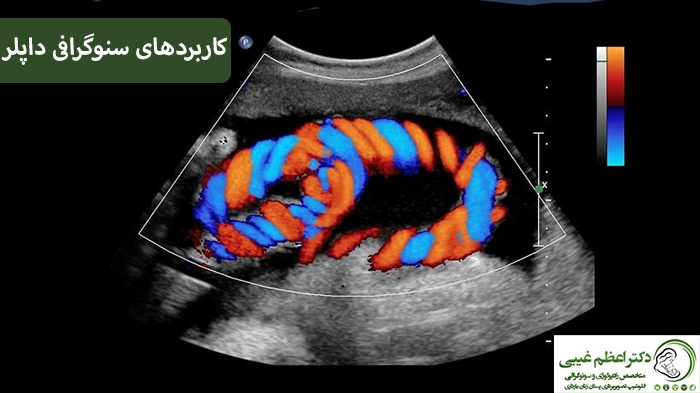

کالر داپلر: داپلر رنگی می تواند به نمایش دادن حرکت، سرعت و مسیر جریان خون کمک کند.

سونوگرافی داپلر یک نوع تخصصی از سونوگرافی است که برای بررسی جریان خون در رگ‌ها و عروق بدن به کار می‌رود. این روش به کمک امواج صوتی با فرکانس بالا می‌تواند سرعت و جهت جریان خون را در عروق نمایش دهد. سونوگرافی داپلر به‌خصوص در تشخیص بیماری‌های مرتبط با جریان خون بسیار کاربردی است. در ادامه انواع کاربرد های این نوع سونوگرافی را بیان خواهیم کرد:

• سونوگرافی داپلر در بارداری برای بررسی جریان خون جفت، بند ناف و قلب جنین استفاده می‌شود تا سلامت جنین و احتمال بروز مشکلات در جریان خون بررسی شود.

کاربرد در دوران بارداری